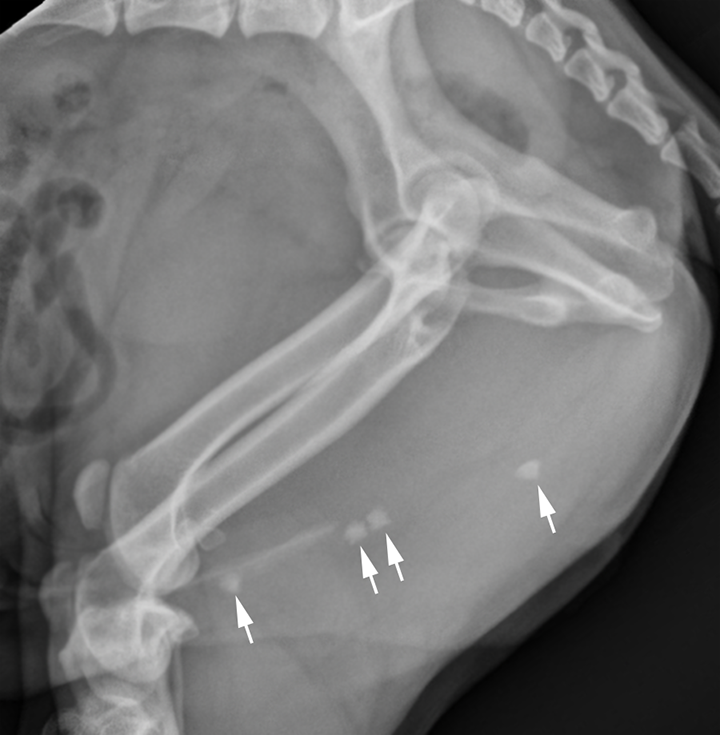

Radiopaque calculi (arrows) inside urinary bladder Download Radiopaque Urinary Calculi — less radiopaque calculi, such as pure uric acid stones and stones composed mainly of cystine or magnesium ammonium phosphate,. This article reviews types of urinary calculi and their imaging appearances, presents direct and. — most renal calculi are made of radiopaque calcium compounds followed by radiolucent uric acid. — although 90% of urinary calculi are radiodense. Radiopaque Urinary Calculi.

Radiography. Multiple, round, variably sized radiopaque masses (arrow Radiopaque Urinary Calculi — although 90% of urinary calculi are radiodense on abdominal radiographs, the sensitivity for the prospective identification of individual. — less radiopaque calculi, such as pure uric acid stones and stones composed mainly of cystine or magnesium ammonium phosphate,. This article reviews types of urinary calculi and their imaging appearances, presents direct and. They may cause pain, nausea,. Radiopaque Urinary Calculi.